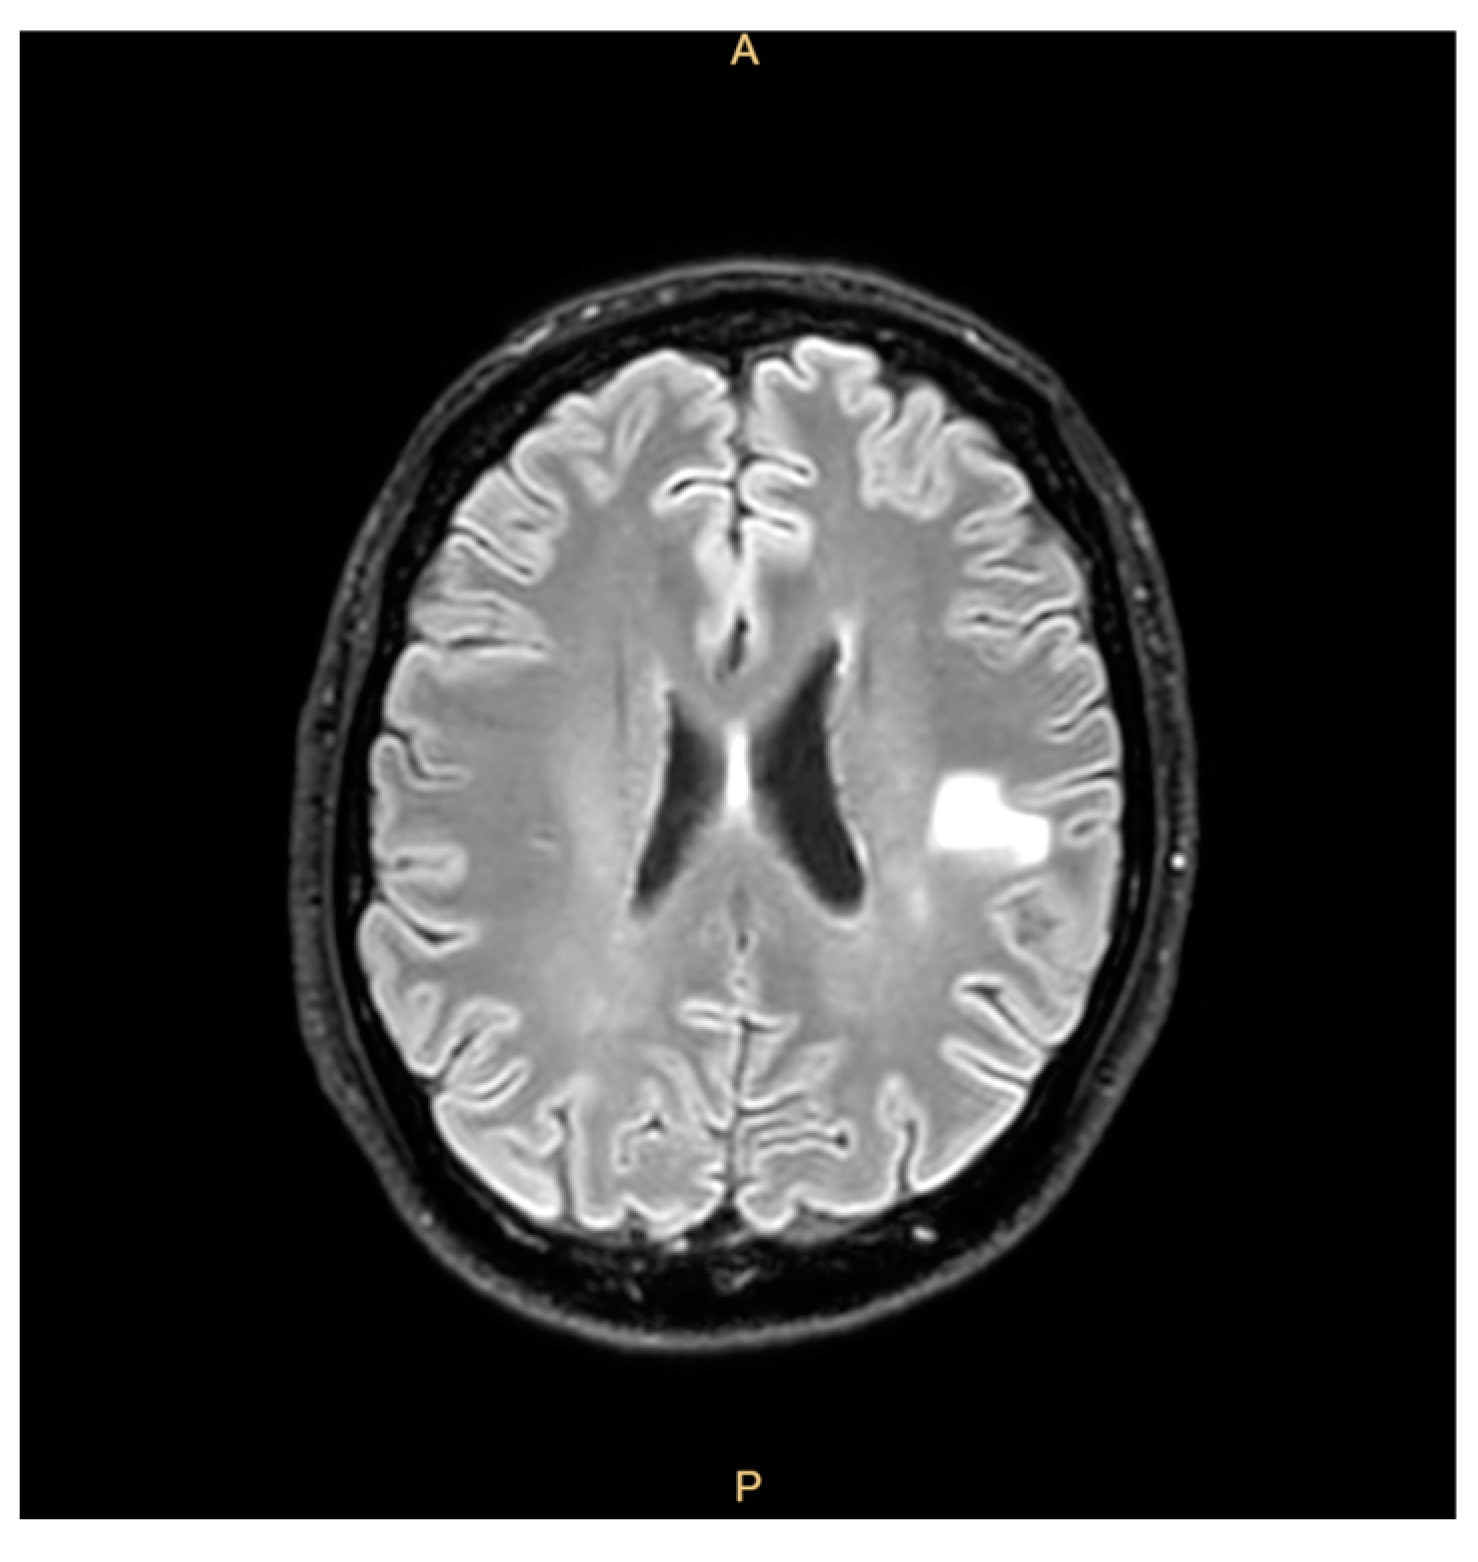

The patient had a past medical history of a prosthetic valve replacement 7 years earlier for a severe aortic insufficiency due to a ventricular septal defect (VSD). Four years later, the patient received a recall notification telling him to come to the hospital as part of an investigation promoted by the Veneto Region; this recall concerned all patients who had undergone major cardiac surgery between 2010 and 2017 (https://www.osservatoriomalattierare.it/malattie-rare/malattia-polmonare-da-micobatteri-non-tubercolari/14390-infezione-da-mycobacterium-chimaera-nella-regione-veneto-i-pazienti-richiamati-sono-1400, accessed on 30 March 2025) and aimed to rule out an infection from MC. However, he decided to decline the invitation to participate in the screening and clinical check, citing his good clinical condition and lack of any signs or symptoms. Two years before the last admission, the patient reported fatigue, weight loss, a cough, and right-arm paresthesia coinciding with cerebral hemorrhagic lesions that were misdiagnosed as mycotic emboli and treated with corticosteroids, with the patient’s condition showing clinical improvement (Figure 1).

Figure 1.

Brain magnetic resonance showing outcomes of hemorrhagic lesions.

After six weeks of treatment, a transesophageal echocardiogram disclosed a resolution of the endocarditic lesions. The patient’s blood count also improved, and a normal blood calcium level was restored. The antimicrobial regimen also led to near-complete regression of cerebral mycotic aneurysms after one month. The antimicrobial treatment was well tolerated and is still ongoing.